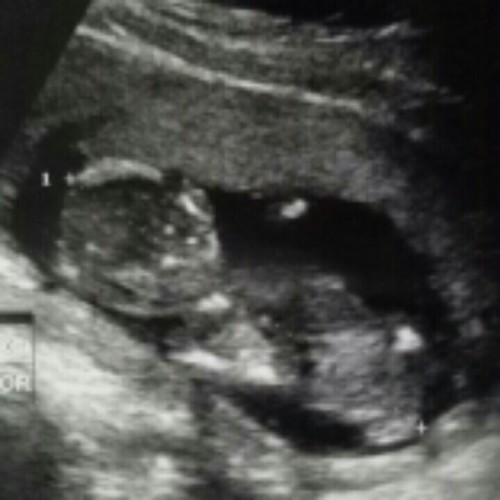

ขอสอบถามหน่อยค่ะ อายุครรภ์ 14 w4d เด็กในท้องขนาดนี้ไหมค่ะ ท้องแรกค่ะ พอดีลองเทียบกับคนข้างๆคือในใบซาวอายุครรภ์ใกล้ๆกัน ของเขาเป็นรูปร่างเด็กแล้วคะ กังวลจังเลยคะ